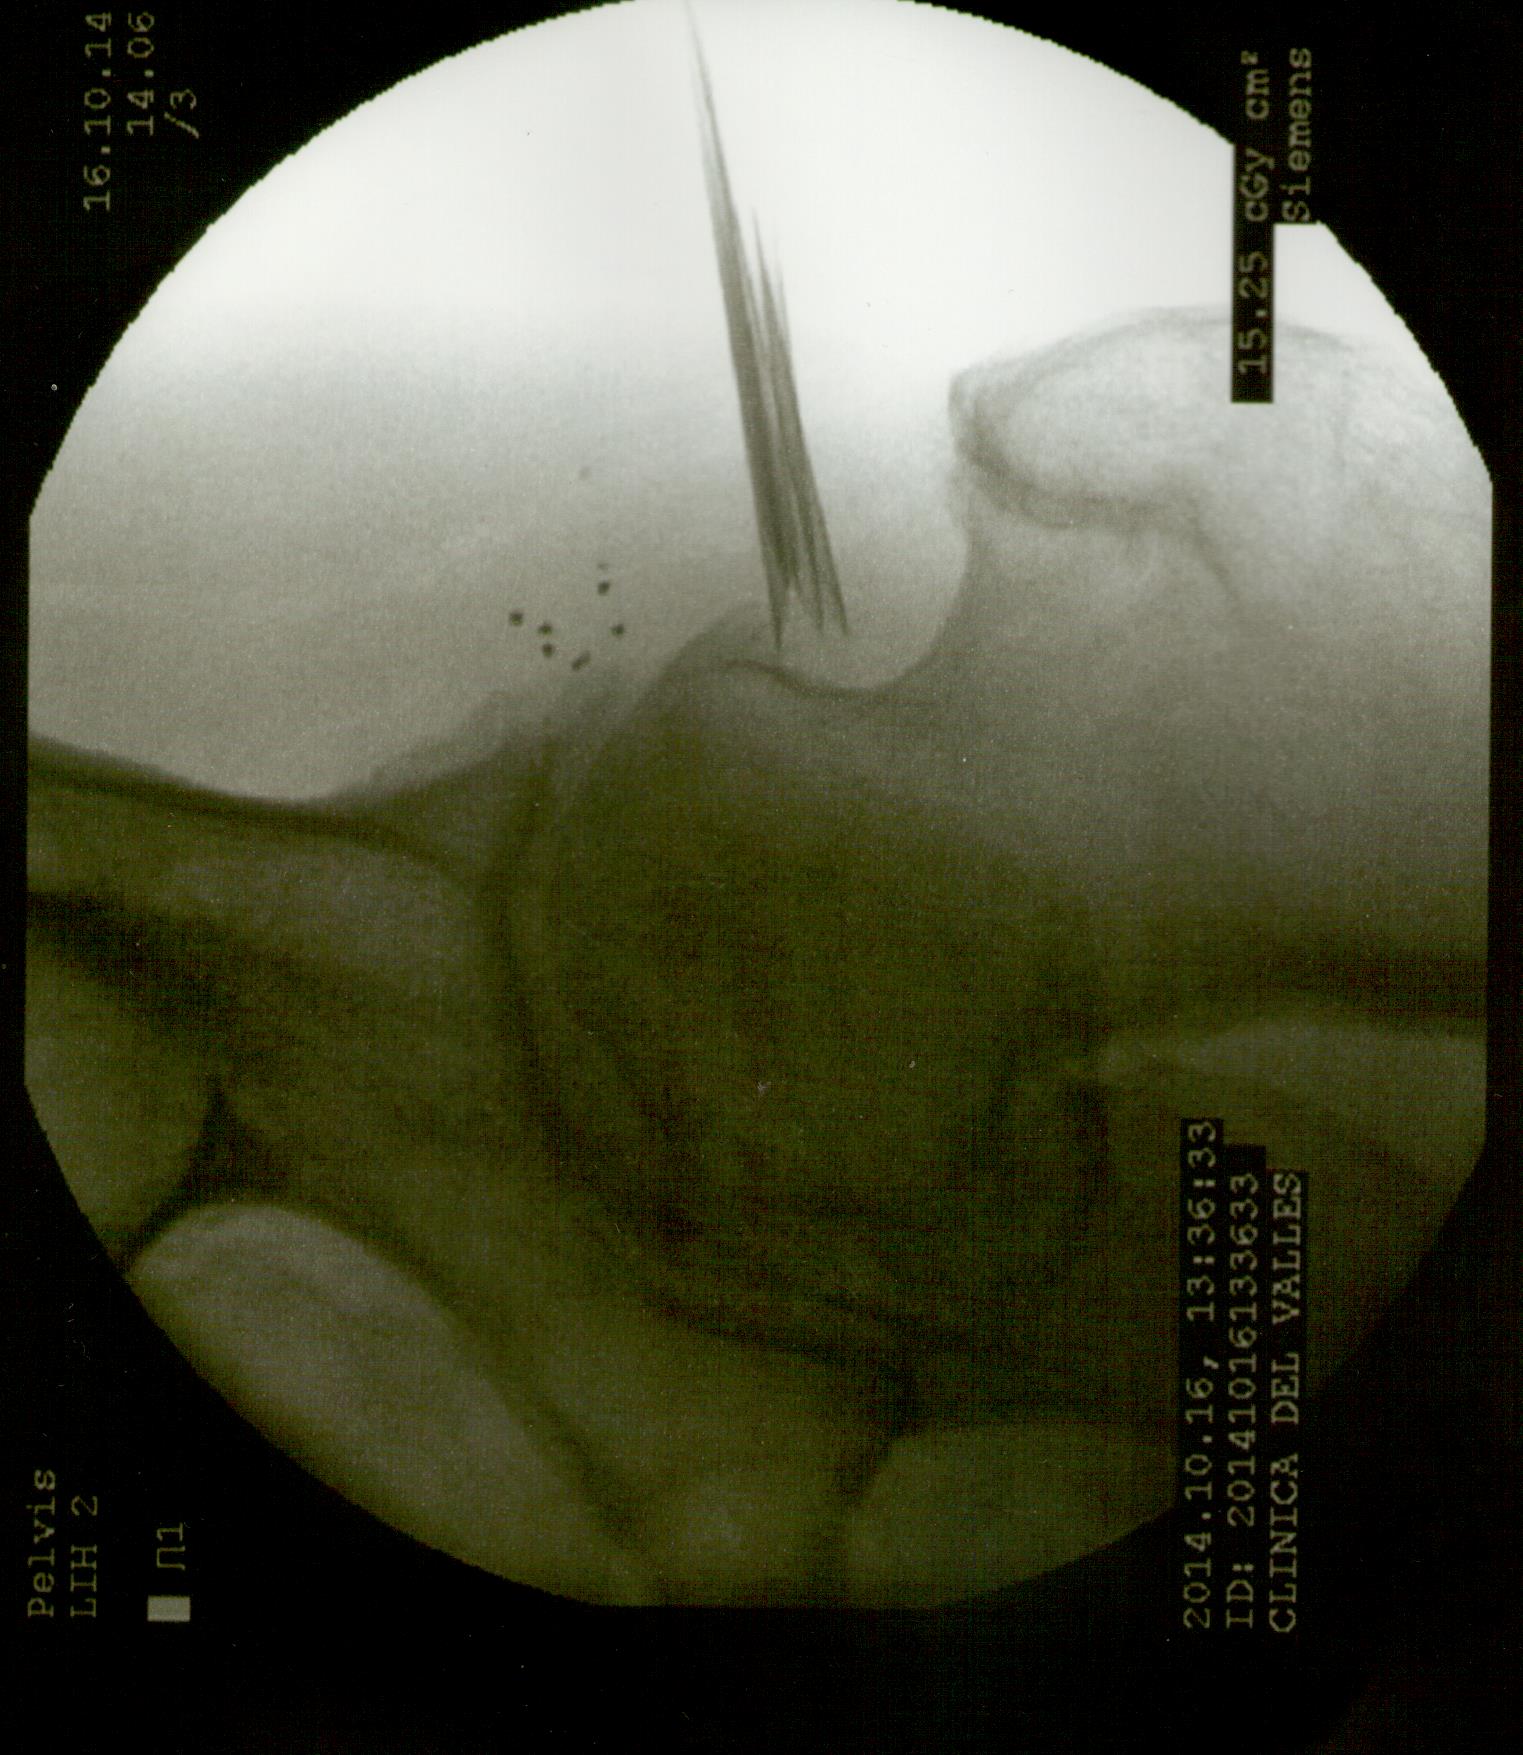

A continuación las imágenes de radioscopía que corresponden al paciente en cuestión. Se observan en primer lugar la colocación de las agujas que vehiculizan los microimplantes, y éstos (pequeños puntos) ubicados próximos a la ceja cotiloidea y a la osteofitosis de la cabeza del fémur.